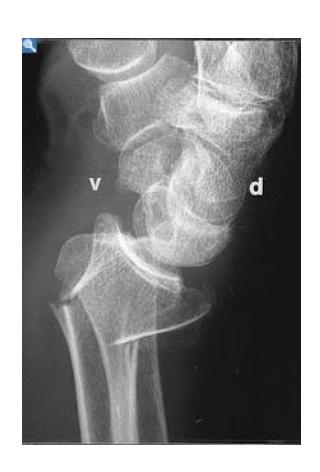

Scaphoid Fracture

Scaphoid Fracture Treatment

- Treatment: Thumb spica cast